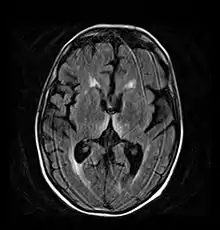

Axial MRI FLAIR image showing hyperintense signal in the mesial dorsal thalami, a common finding in Wernicke encephalopathy. This patient was nearly in coma when IV thiamine was started, he responded moderately well but was left with some Korsakoff type deficits.